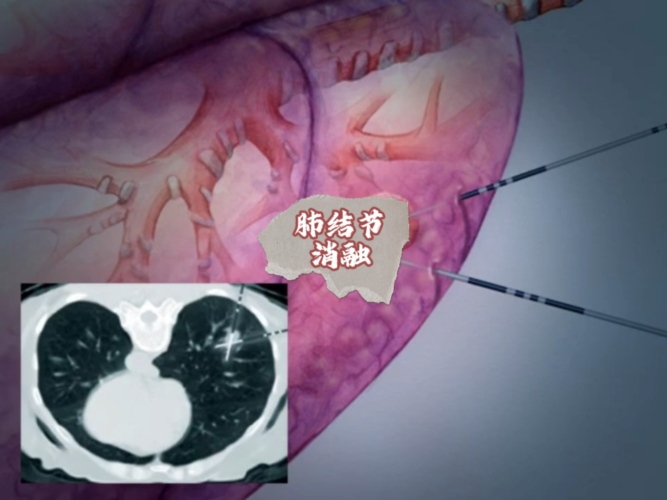

医学硕士,1.擅长手汗症个体化综合治疗。2.擅长肺小结节无痛定位、切除、快速康复一站式介入-手术一体化治疗方案。3.擅长肺癌手术为主综合治疗。4.擅长达芬奇机器人-复合手术室联动肺结节手术。